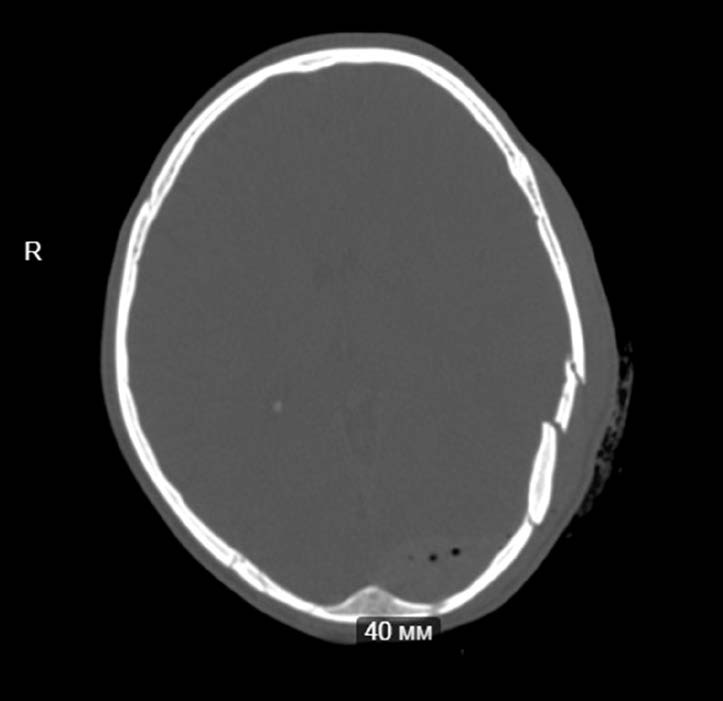

На снимке по МСКТ головного мозга в аксиальной проекции определяется депрессионный вдавленный многооскольчатый перелом лобной пазухи.